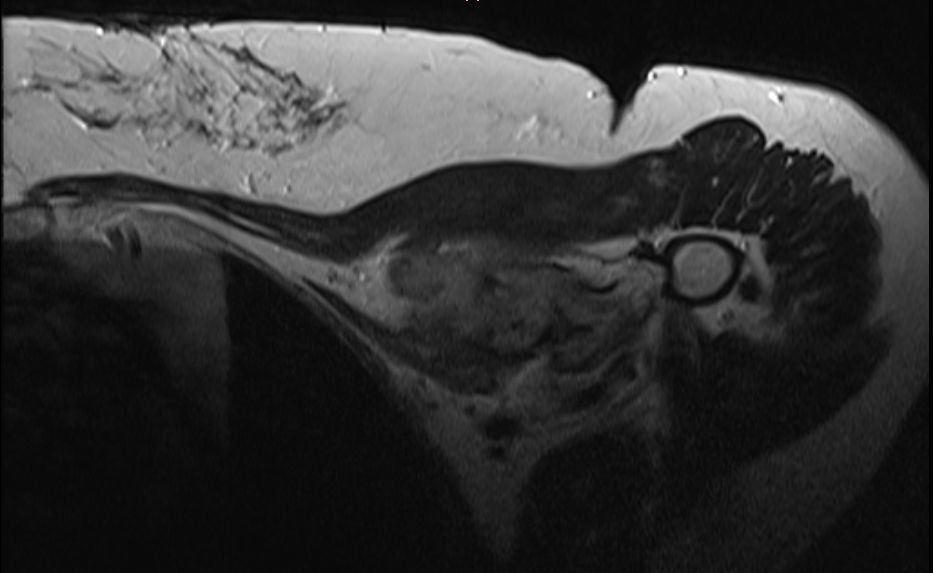

| Diagnostik | 56-jährige Frau mit einer derben, wenig verschieblichen Tumorbildung untergalb der linken Clavikula. ![]() |